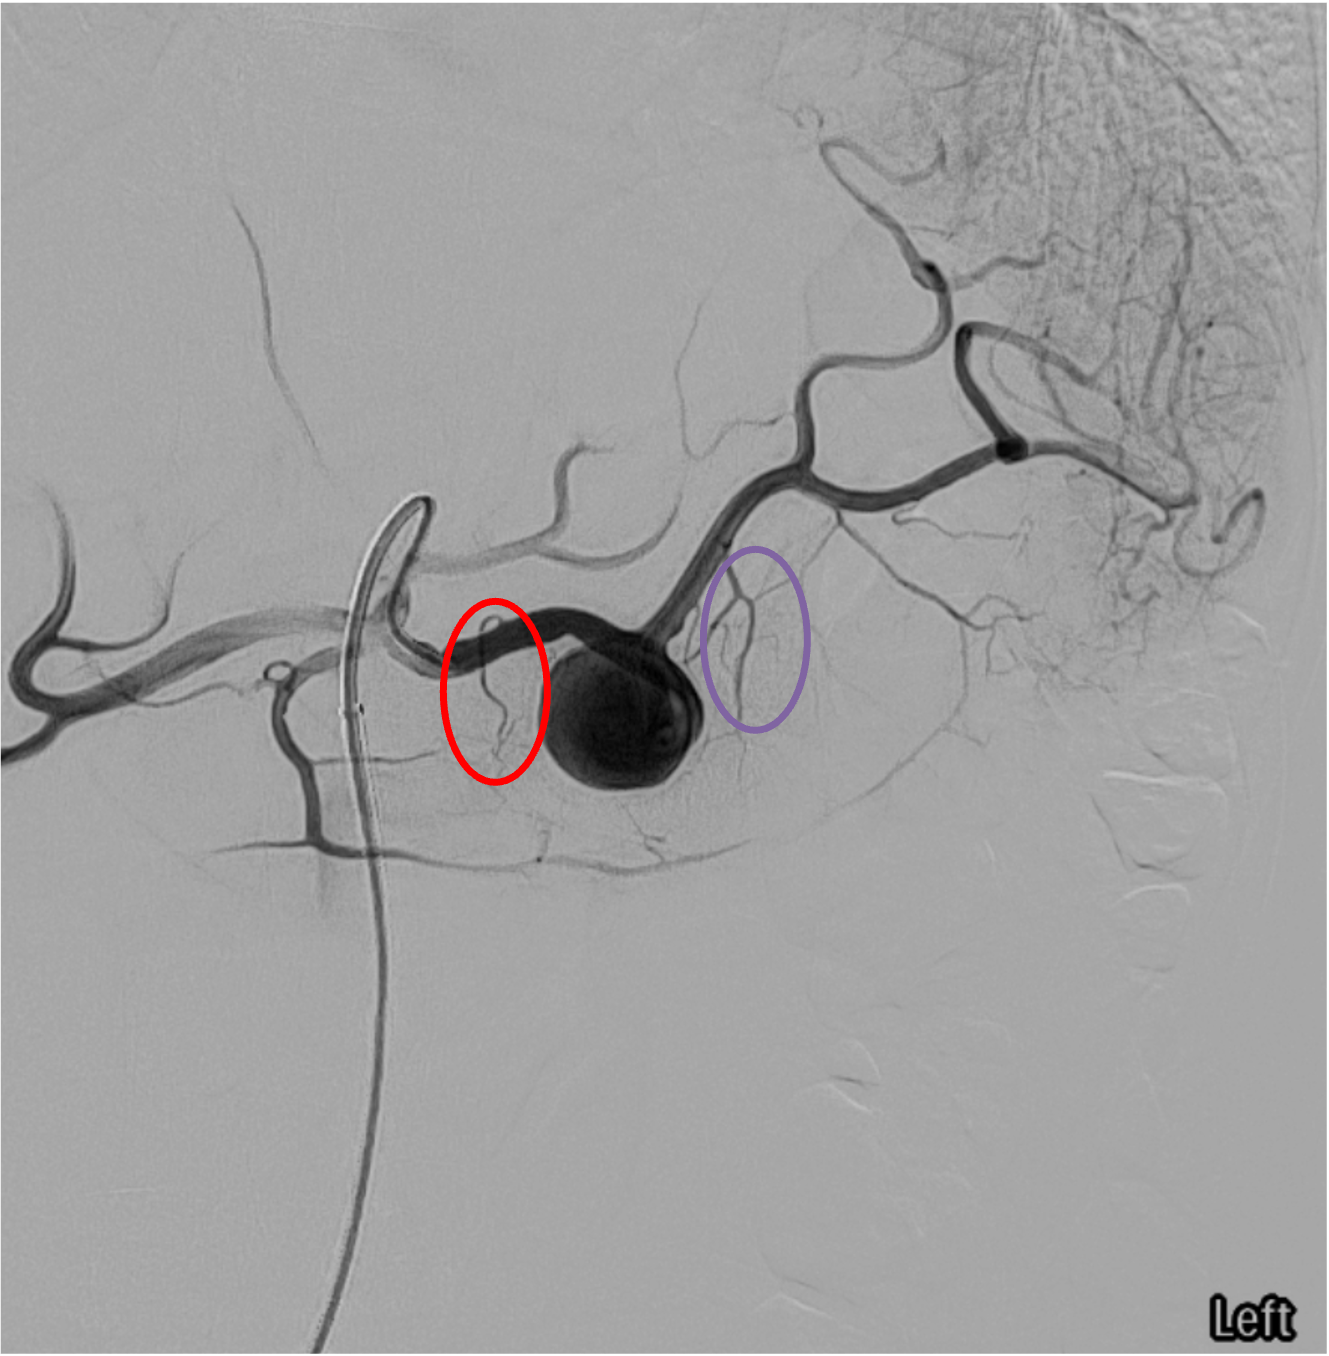

Signs of Vascular Injury on Angiography

- Active extravasation: contrast blush that persists and increases in density on subsequent phases; irregular, amorphous contrast pooling outside the vascular lumen

- Pseudoaneurysm (PSA): focal, well-circumscribed contrast collection that fills and empties with arterial phase; contained rupture

- Arteriovenous fistula (AVF): early opacification of splenic or portal vein during arterial phase

- Vessel truncation / irregularity: abrupt cutoff or spasm of intrasplenic branches suggesting parenchymal disruption